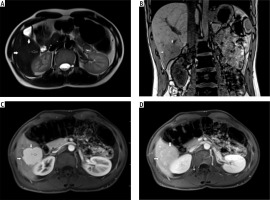

Fig. 1

A) T2-weighted image in transverse plane, focal lesion in right lobe of liver (full white arrows). Signal of lesion slightly higher in relation to the liver parenchyma. In the central part, a small area with lower signal (empty white arrow). B) T1-weighted image in coronal plane, focal lesion in right lobe of the liver (full white arrows). The lesion signal is lower in relation to the liver parenchyma. In this sequence, a well-visible hyposignal central fibrous scar and spoke spaced connective tissue septa are clearly visible. C) T1-weighted image at an early stage after administration of contrast agent. Acquisition in the transverse plane, focal lesion in the right lobe of the liver (full white arrows). The lesion is enhanced intensively in relation to the liver parenchyma. Hyposignal scar remains in the center of the lesion. D) T1-weighted image in the late phase after administration of contrast agent. Acquisition in transverse plane. Focal lesion in the right lobe of the liver (full white arrows). Enhancement of the lesion and the liver parenchyma in this phase is similar. Lesion was qualified as focal nodular hyperplasia (FNH)